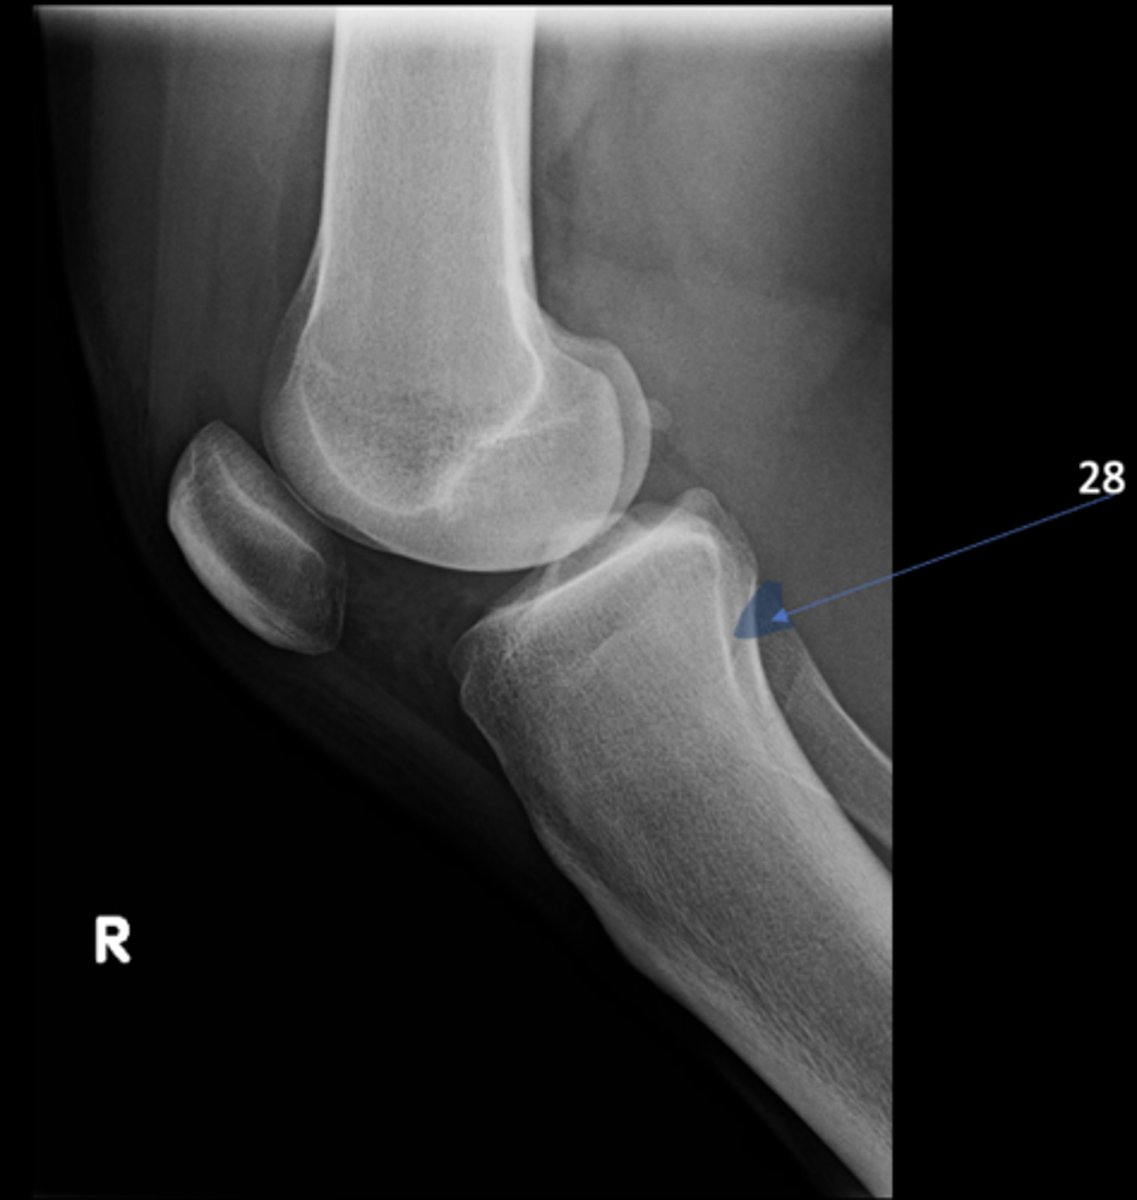

Right lateral knee

View?

<p>View?</p>

68

New cards

Tibial tuberosity

ID 19

<p>ID 19</p>

69

Intercondylar eminence

ID 20

<p>ID 20</p>

70

Both tibial condyles

ID 21

<p>ID 21</p>

71

Fibular head

ID 22

<p>ID 22</p>

72

Apex of patella

ID 24

<p>ID 24</p>

73

Superior aspect of patella

ID 25

<p>ID 25</p>

74

Ludloff's spot/patch

ID 27

<p>ID 27</p>

75

Apex of fibular head

ID 28

<p>ID 28</p>